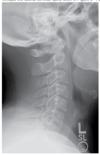

When imaging the cervical spine in extension, as shown in the image below, patients should be instructed with which breathing instructions:

Critique the lateral cervical spine seen in Figure 2–1 and select the most correct statement below. A - The chin has been depressed too much. B - The chin needs to be extended more. C - The head is tilted. D - The shoulders are not depressed enough.

D - The shoulders are not depressed enough. The lateral projection of the cervical spine requires that the MSP be parallel to the IR and the MCP be perpendicular to the IR. The chin must be elevated enough so as not to superimpose the mandibular angles on cervical structures—yet not so much that the base of the skull obscures cervical structures. The degree of flexion/extension is appropriate in this image; no cervical structures are obscured. The vertebrae are symmetrical—no rotation is present. However, C7 is not clearly delineated, and its all-important articulation with T1 is not visible. This indicates that the shoulders are not sufficiently depressed. ``